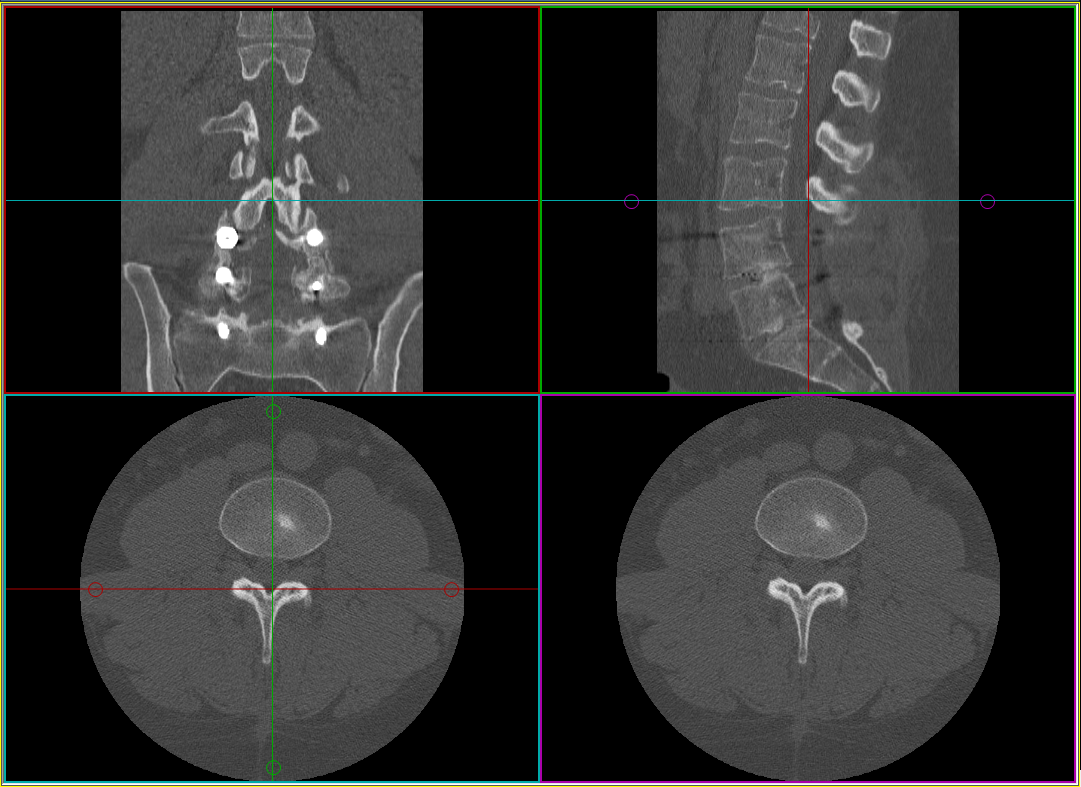

Az MPR létrehozása után a képkocka négy kisebb kockára oszlik. Minden keret egyetlen ortogonális nézetet (szagittális, koronális és axiális), plusz egy ferde szögű nézetet tartalmaz. A ferde képkocka az Eredmények ablak, ezt egy lila lokalizáló jelzi a coronális nézetben. A másik három kocka vezérlőablak. Olyan színkoordinált lokalizálók állnak rendelkezésre, amelyek a vonal színét az adott síkban lévő képet tartalmazó kocka színéhez illesztik. Ezekkel a lokalizálókkal mozgathatja és elforgathatja a ferde képet.

A ferde képkockában forgatási funkció érhető el a végleges kívánt prezentációs nézet eléréséhez.

A nagyítás és a pásztázás funkció a ferde nézethez is rendelkezésre áll.